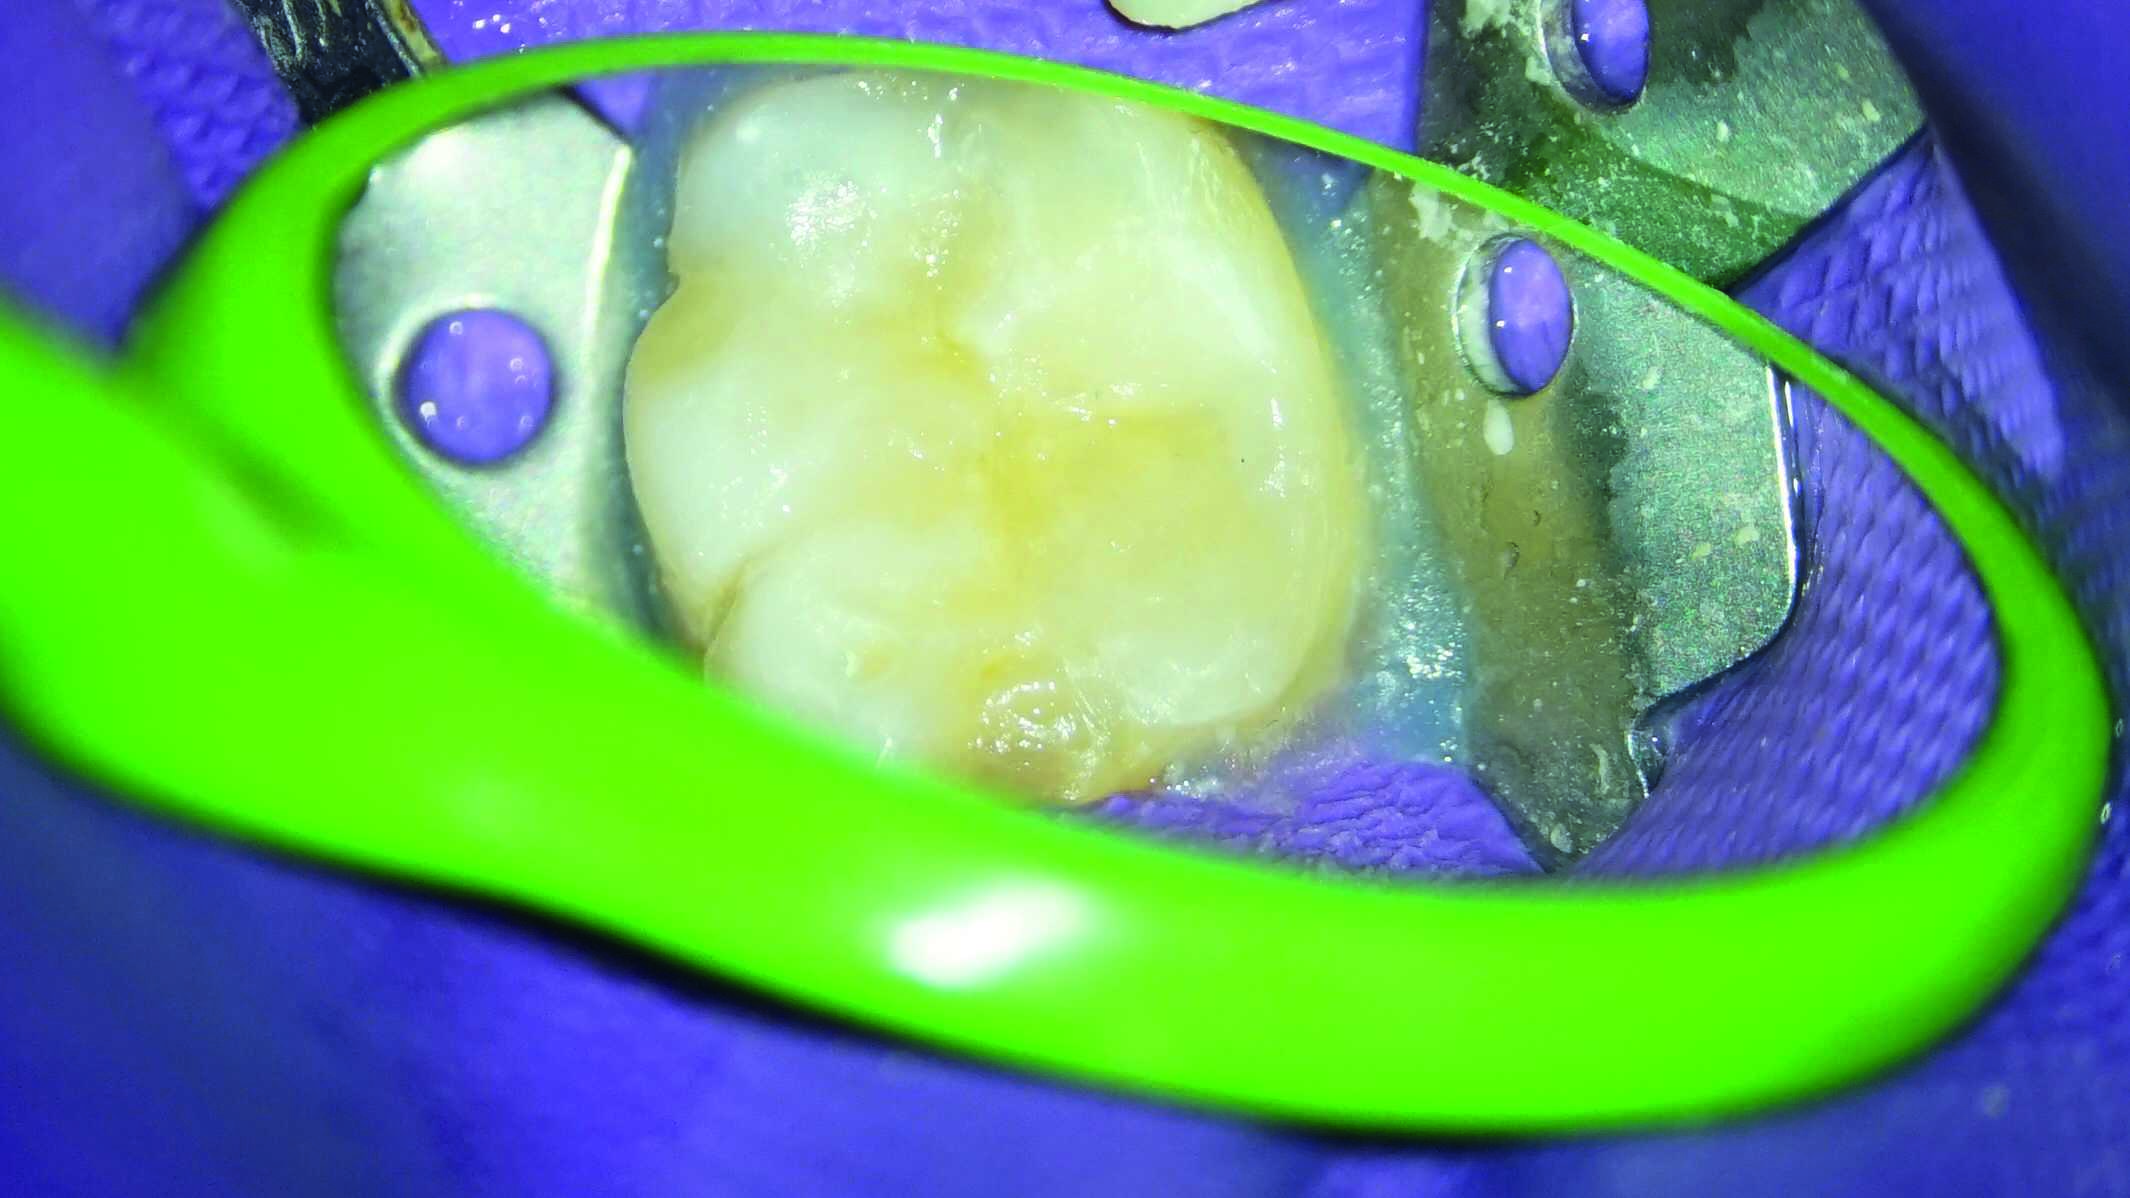

Direct Restoration with Pulp Expose Pulp Capping Dokter Gigi Griya Direct Pulp Capping Dentist Near Me Exposures may be due to deep caries (decay), trauma, or mechanical such as. Third party financingpersonal pricing options direct pulp capping occurs only on permanent teeth when the pulp becomes exposed. The american academy of pediatric dentistry (aapd) recommends using a direct pulp cap only on a primary tooth when exposure results from mechanical trauma. — root canal. Direct Pulp Capping Dentist Near Me.

Direct Pulp Capping POP Dentistry Direct Pulp Capping Dentist Near Me direct pulp capping can be performed when a pulp exposure occurs. The american academy of pediatric dentistry (aapd) recommends using a direct pulp cap only on a primary tooth when exposure results from mechanical trauma. Third party financingpersonal pricing options — root canal treatments are typically performed to address issues related to the dental pulp, which is the. Direct Pulp Capping Dentist Near Me.

Direct Pulp Capping with BIOBulk technique Direct Pulp Capping Dentist Near Me Exposures may be due to deep caries (decay), trauma, or mechanical such as. The american academy of pediatric dentistry (aapd) recommends using a direct pulp cap only on a primary tooth when exposure results from mechanical trauma. the direct pulp capping procedure involves applying a medicated material directly to the exposed pulp of a tooth. as an alternative. Direct Pulp Capping Dentist Near Me.